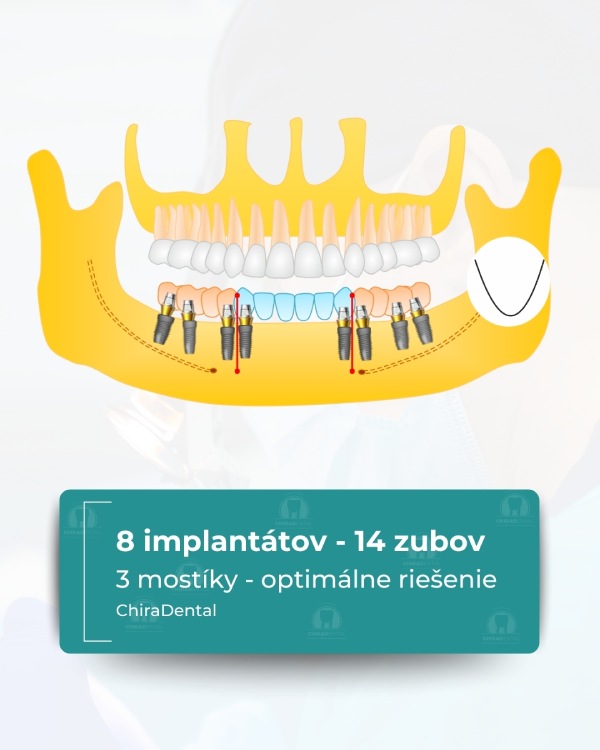

Moderné technológie umožňujú rýchlo, spoľahlivo a esteticky obnoviť celú čeľusť, a to aj v zložitých prípadoch. Ponúkame niekoľko kompletných rehabilitačných systémov založených na počte implantátov a úrovni fixácie budúcej štruktúry. Možnosť 1 - All-on-4 (Základné riešenie) Táto metóda je vhodná pre pacientov so zníženým objemom kosti alebo pre tých, ktorí chcú nové zuby čo najrýchlejšie. Čo robíme: Inštalujeme 4 implantáty do hornej alebo dolnej čeľuste; V prípade potreby vykonáme augmentáciu kosti a plastiku ďasien počas tej istej návštevy; Nasledujúci deň odoberieme odtlačky pre dočasnú štruktúru; Po 3-5 pracovných dňoch pacient dostane dočasné kovovo-akrylátové zuby na dlhodobé nosenie. Výsledok: približne 10 nových zubov, ktoré umožňujú pohodlné žuvanie a úsmev. Po 3-6 mesiacoch vykonávame trvalé rekonštrukcie s použitím kovovo-keramiky alebo zirkónu. ⭐ Možnosť 2 — All-on-6 (štandardné riešenie) Optimálna možnosť pre pacientov, ktorí vyžadujú väčšiu stabilitu a väčšiu žuvaciu záťaž. Čo robíme: Inštalácia 6 implantátov so súčasnou augmentáciou kosti a ďasien; Odtlačky sa robia nasledujúci deň;Dočasné kovovo-akrylátové korunky sa inštalujú po 3-5 dňoch.

Výsledok: kompletný oblúk 14 zubov. Definitívna rekonštrukcia (kovovo-keramika alebo zirkón) sa vykonáva po 3-6 mesiacoch.